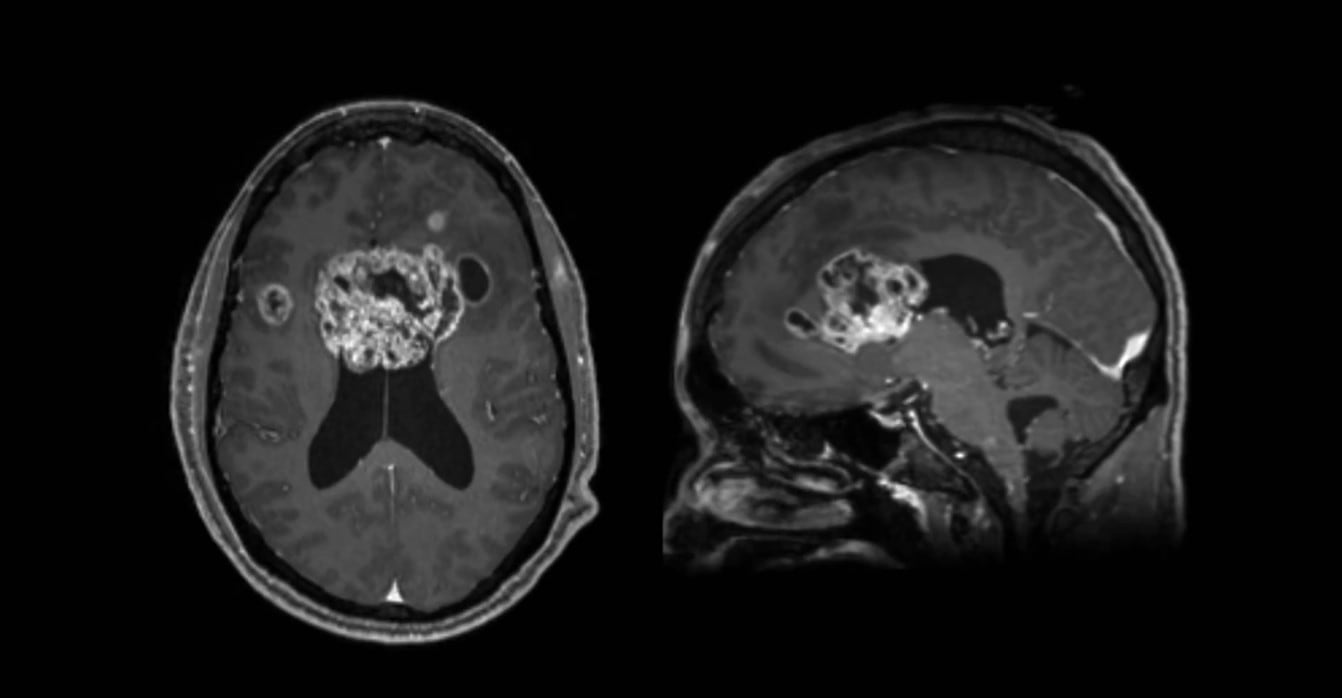

Lo que siguió fue la consulta médica, en la que se descubrió el tumor cerebral mediante una tomografía computarizada y el diagnóstico de glioblastoma avanzado. Su esposo, Brunson Green, contó en el reportaje las palabras de los doctores: “Fuimos a urgencias y en cinco minutos nos dijeron que tenía un bulto del tamaño de una pelota de béisbol en medio del cráneo”.

El ex jugador describió a su enfermedad como “una mariposa que prácticamente lo invadió todo”, dando a entender la velocidad con la que se propagó el cáncer en su cuerpo. «Había terminado un tratamiento de radioterapia, pero el glioblastoma aprendió cómo volver a crecer. Había duplicado su tamaño en unas dos o tres semanas. Recuerdo que mi hermano me hablaba de la batalla a la que me iba a enfrentar. Me decía: ‘Tienes que luchar’. Y eso es lo que he hecho toda mi vida, luchar», prosiguió.